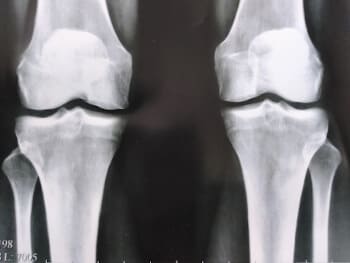

দুই বছর আগে আমি প্রথম আমার হাঁটু এবং নিতম্বে হালকা ব্যথা অনুভব করেছি। ব্যথা তীব্র ছিল না, তাই আমি এটিতে খুব বেশি মনোযোগ দিইনি... দেখা যাচ্ছে যে জয়েন্টের রোগগুলি খুব বিপজ্জনক এবং অবিলম্বে চিকিত্সা করা উচিত, আমার মতো অপেক্ষা করা উচিত নয়। একদিন আমার হাঁটুতে হালকা কিন্তু তীক্ষ্ণ ব্যথা হয়েছিল, এবং আমার নিতম্বের জয়েন্টটি গুরুতরভাবে আঘাত করতে শুরু করেছিল, এবং আমি ভেবেছিলাম যে কিছুই ভুল ছিল না, এটি চলে যাবে, যেমন এটি সাধারণত হয়। আমি ওষুধ ও মলম কিনে ব্যবহার শুরু করলাম। এক সপ্তাহ বা তার পরে, আমার অবস্থা তীব্রভাবে খারাপ হয়ে যায়, ব্যথা অসহ্য হয়ে ওঠে, আমার নিতম্বের জয়েন্টে তীব্র ব্যথা শুরু হয় এবং আমি প্রথমবারের মতো ডাক্তারের কাছে যাওয়ার সিদ্ধান্ত নিয়েছিলাম। তারা আমাকে একটি রোগ নির্ণয় দিয়েছে যা সস্তা ছিল না এবং আমার ডাক্তার পরীক্ষার ফলাফল দেখে আমাকে বলেছিলেন:

"আপনি আগে উপসর্গ উপেক্ষা কেন? আপনার অস্টিওআর্থারাইটিস আছে! অস্টিওআর্থারাইটিস, আপনি যদি অক্ষম হতে না চান তবে আপনাকে নিতম্ব এবং হাঁটু অস্ত্রোপচার করতে হবে!